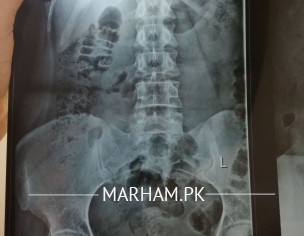

Asking For Self, Female 24, Islamabad

for approximately a wk, i was having discomfort lying supine, it was not pain but discomfort as i can feel my sacrum, a part of it bulging kind of. i thought its a misalignment. i feel slight back pain on long standing or sitting straight for a while for 2 days. is this lumbosacral spine xray normal?

Xrays seem to be fine . Many things have to be accounted for to get ro the bottom of the problem ... findling a solution on comments wont help much . I recommend getting an appointment

detailed history is required to find out the cause then it's treatment rest of these x rays seems ok . if u are interested then take appointment through Marham